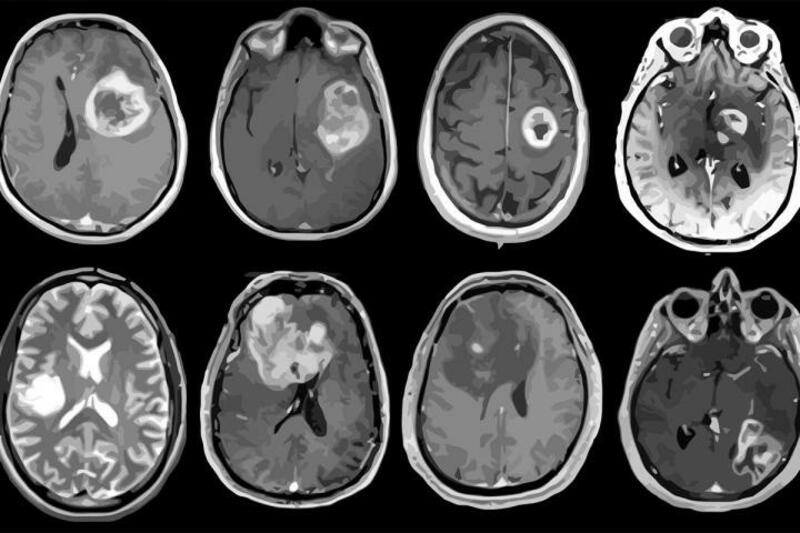

Desde la SEN advierten de que, este tipo de tumores que aglutinan más de 120 tipos en el sistema nervioso, en los últimos años se ha observado un incremento en el número de casos por año debido, principalmente, a la mejora de las técnicas de imagen -lo que ha permitido perfeccionar su diagnóstico-, y al progresivo envejecimiento de la población.

Y es que la edad de aparición de los tumores cerebrales presenta un pico en la edad pediátrica, pero también un aumento progresivo con la edad en adultos, hasta alcanzar su máximo de incidencia entre la sexta y la séptima década de la vida. Se estima que, en la actualidad, en España hay alrededor de 20.000 personas que padecen algún tipo de tumor cerebral, clasificado bien como un tumor primario (originado en el cerebro) o como un tumor metastásico (originado en otras partes del cuerpo, pero que se ha diseminado al cerebro).

Los tumores cerebrales suponen aproximadamente el 2% de todos los cánceres diagnosticados en adultos y el 15% de los diagnosticados en niños, lo que le convierte, durante la edad pediátrica, en el segundo tipo de cáncer más detectado después de la leucemia. En todo caso, aunque no son los tumores más frecuentes, tienen un alto impacto en la vida de las personas que los padecen.